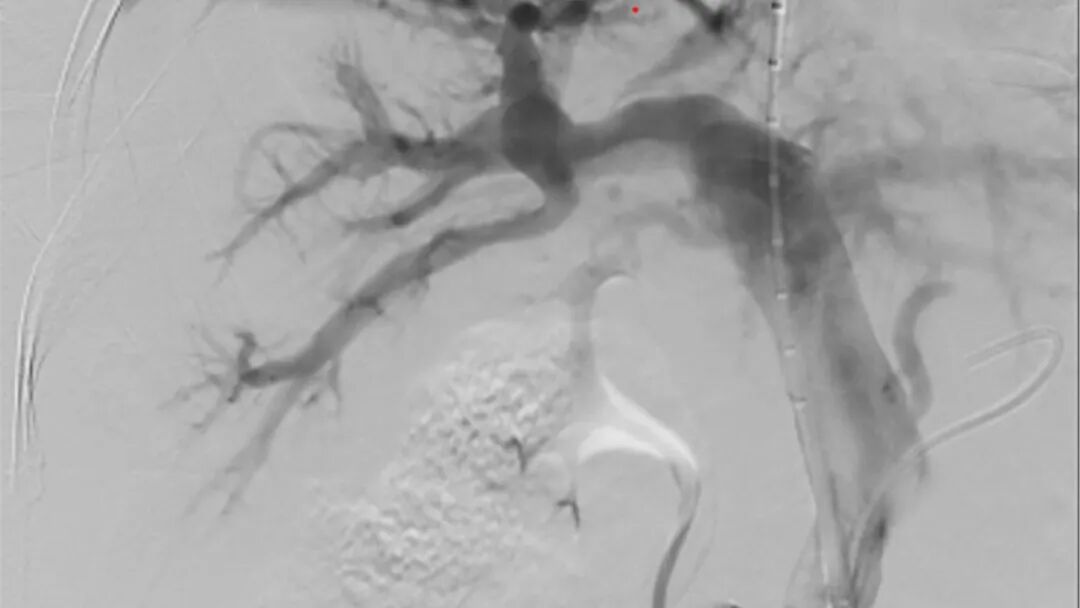

手术当晚,挑战超乎想象。术中,李家平教授发现赵先生的肝脏严重萎缩,血管扭曲变形,门静脉右支被血栓堵了90%,操作空间极为狭小。李家平教授当机立断,决定从左支突破,但左支的血管又细又与门静脉紧密相邻,稍微扎偏一点就可能导致严重出血。关键时刻,李家平教授凭借精湛的技术和丰富的经验,像穿针引线一样,精确地从肝右静脉精准“穿针”到门静脉左支矢状部,每一个动作都精准无误,成功架起支架。

术后当天,赵先生门静脉的压力就下降明显;第二天,原本鼓胀的肚子明显变小,可以下床走动;第三天,血小板和白细胞数值也慢慢回升,各项指标明显好转,能喝粥了。现在,赵先生已经出院回家。